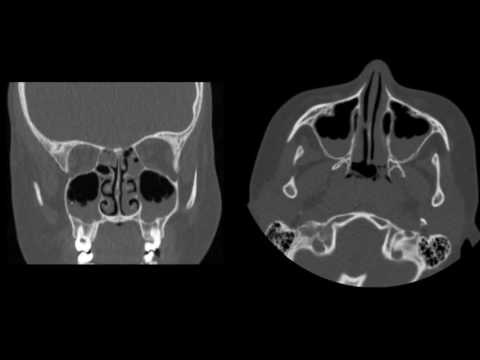

Sinüzit Nedir?